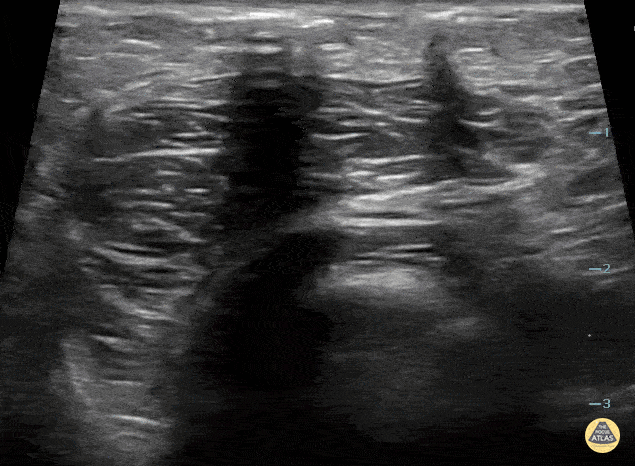

11 yo F presents arm pain after accidentally stabbing herself in the arm with a hair pin. On exam she had erythema and crepitus of the site. POCUS shows dirty shadow consistent with necrotizing fasciitis. She was taken to the OR for debridement. Contributor: Paul Khalil, MD Nicklaus Children's Hospital @khalil3paul